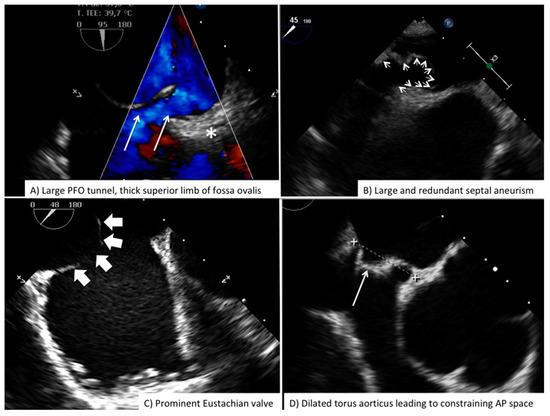

3. PFO

3.2. Perioperative Monitoring

| Before vascular access | Free LA appendage Normal aortic and mitral valve No intracardiac mass Atrial septal aneurysm Eustachian valve Chiari Network Accessory fenestration Antero-posterior septal distance | Free LA appendage No significant mitral valve disease Atrial septal aneurysm Eustachian valve Chiari Network Assess border features Multifenestrated ASD Confirm normal pulmonary vein anatomy Bidimensional and color-based shortest and largest ASD diameter 3D-based shortest and largest ASD diameter |

| After vascular access | Confirm right-to-left shunt at intracardiac bubble study Confirm correct tunnel wiring Confirm wire position in the proper pulmonary vein PFO tunnel amplitude and length | Confirm wire position in the proper pulmonary vein Balloon sizing in stop-flow condition |